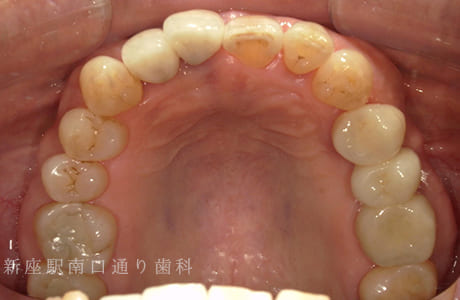

CASE.04

右上にフルジルコニアブリッジで

修復した症例

術前

術中

術後年

- 主訴

- 歯がないところを治したい

- 治療法

- 右上にフルジルコニアブリッジで修復

- 治療期間

- 1ヶ月半

- 費用

- ¥280,000(税込)

【リスク・副作用】

過度の咬合や衝撃で割れることがあります。治療直後は歯や歯茎に一時的な違和感や痛みが出ることがあります。